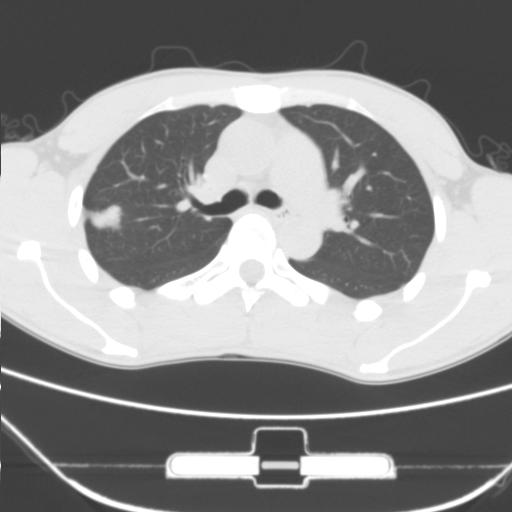

标题: CT25483:肺部病变 请指教

车祸伤者

周围型肺ca与炎性假瘤待鉴别。建议穿刺病理检查

缺乏病史,症状体征,但这个孤立结节具备了几乎所有的恶性征象:分叶,毛刺,空泡征,胸膜凹陷征,血管集束。